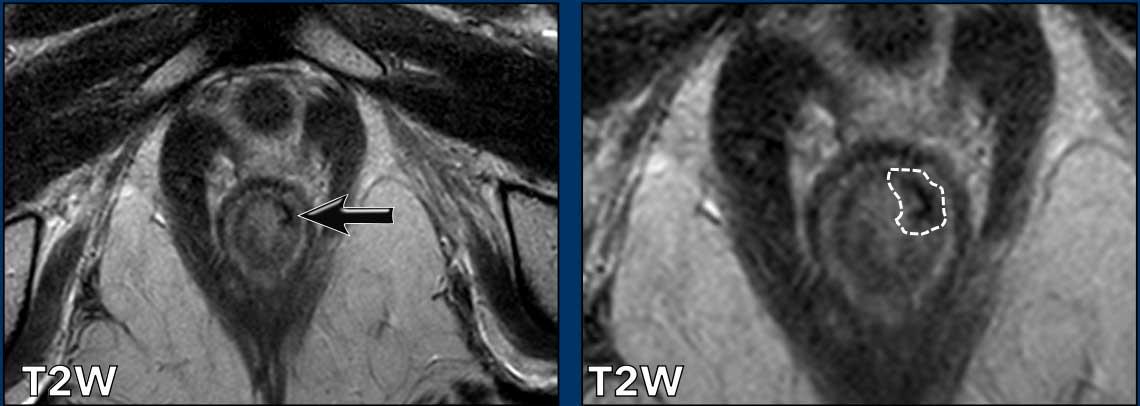

Hình ảnh

Đây là hình ảnh ung thư hậu môn trước hóa xạ trị.

Tiếp tục xem hình ảnh sau điều trị…

Hình ảnh sau CRT

Ghi nhận đáp ứng hoàn toàn với chỉ một vùng xơ hóa mỏng nhỏ tại vị trí khối u cũ ở vị trí 1-3 giờ trong cơ thắt trong (mũi tên).

Không có dấu hiệu hạn chế khuếch tán (cuộn ảnh).

Phần còn lại của cơ thắt trong cho thấy tín hiệu trung gian đến cao mờ nhạt, biểu hiện phù nề do xạ trị (không có hạn chế khuếch tán).

Tiếp tục xem hình ảnh sau 2 năm…

Ghi nhận tái phát tại chỗ 2 năm sau khi hoàn thành CRT.

Lưu ý rằng tổn thương tái phát có kích thước lớn hơn khối u nguyên phát.

Cần thực hiện phẫu thuật cắt bỏ bụng-tầng sinh môn mở rộng sau khi xạ trị lại để cứu vãn trường hợp tái phát này.